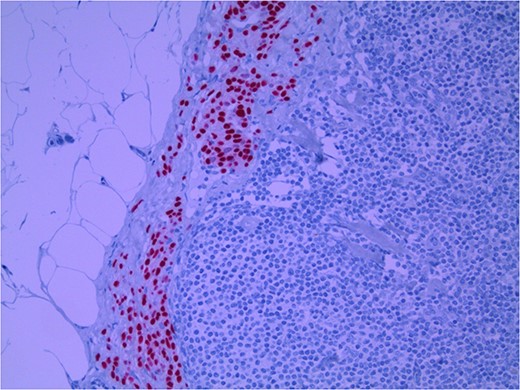

Lymph node specimens were sent for haematoxylin and eosin (H&E) staining (Fig. 3) and IHC analysis. The sections showed mild reactive changes and benign intracapsular nevoid rests. IHC analysis showed that these cells were negative for HMB-45 (Fig. 4) and were positive for both Sox10 and p16 (Figs 5 and 6). Consensus at the Multidisciplinary Team Meeting was that the appearance was in keeping with benign naevoid rests as opposed to melanoma deposits, given the location of the cells, morphology and immunohistochemistry. Surveillance was recommended.

Lymph node with IHC using HMB-45 stain, not staining subcapsular region melanocytic cells; × 200 magnification.